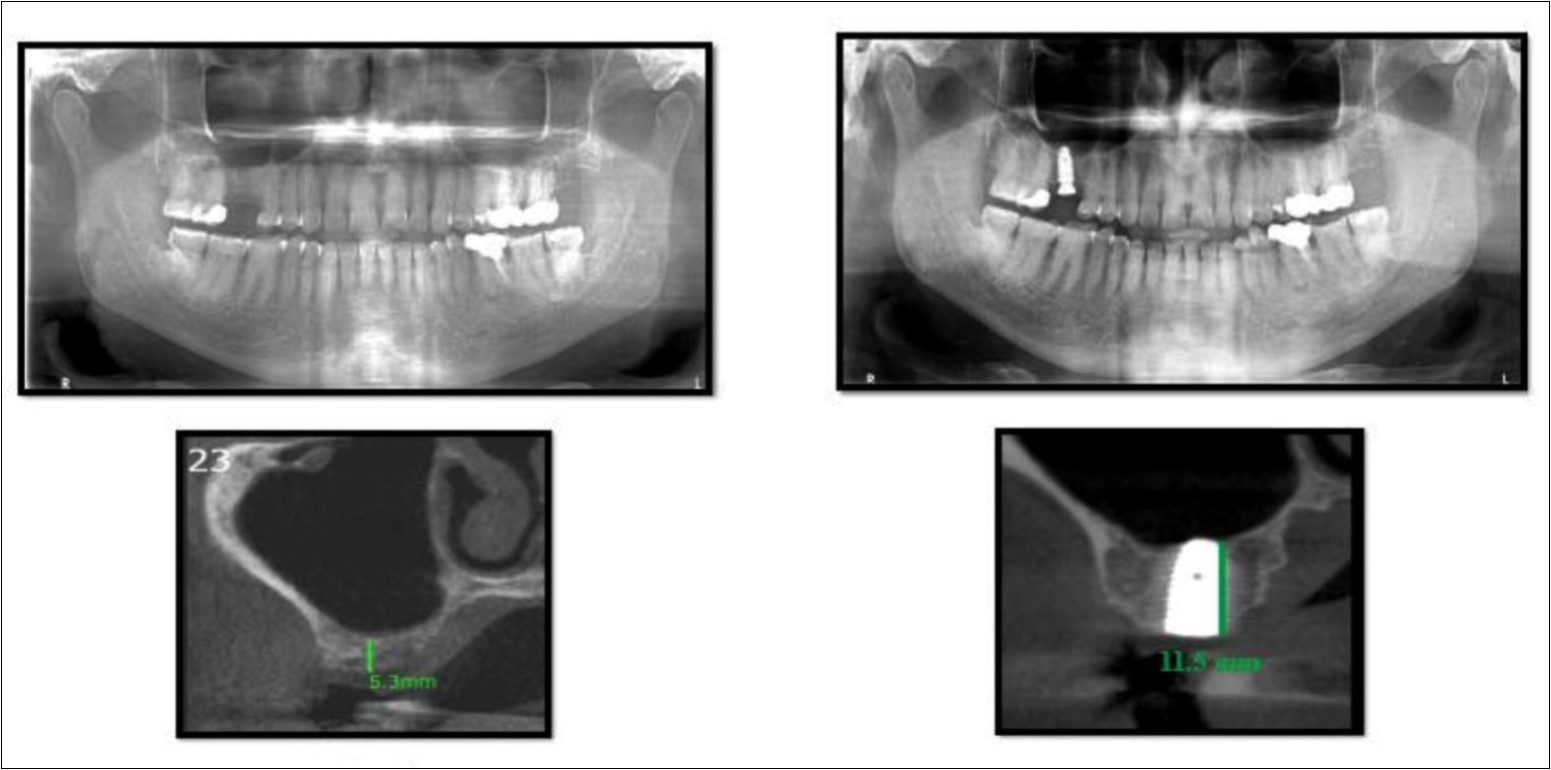

Sinus augmentation procedures were carried-out in 17 patients seeking implant options for oral rehabilitation including 10 for direct and 10 of indirect procedures (n=20, 10 direct and 10 indirect). The study comprised of 43% females and 57% males with a mean age of 46.07 years. A total of 17 patients (20 segments) satisfying the above criteria requiring placement of implants in atrophic maxilla/ increased pneumatisation of the maxillary sinus were selected for the study. The patients were informed about the study including the use of the synthetic graft material and their approval was sought before their inclusion in the study. A written informed consent was obtained from each of the participating patients. For each patient, a detailed case history was taken including chief complaint, history of presenting illness and medical history and personal history. A thorough clinical examination, including systemic and regional examination, was done. Patients with sinus pathology, previous sinus surgeries, chronic smokers, patients under 18 years of age, and with underlying systemic conditions which contradicts any surgical procedures were excluded from the study. The type of sinus lift was decided based on the pre-operative residual bone height evaluated radiographically. The residual bone height was recorded using CBCT scan and a computer based software where the measurements were made from the crest of the ridge till the sinus floor lining. Indirect sinus augmentation was done in patients with a bone height of <9mm but more than or equal to 5mm. Patients with a bone height of less than 5mm were taken up for direct sinus augmentation. The period of edentulousness varied from 6 months to 12 months. Apically tapered, commercially pure titanium implants (Life Care Devices Private Limited Mahim, West Mumbai, India) were used for patients undergoing indirect sinus augmentation. The length of implant was 8, 10, and 11.5 with diameters of 3.5, 4.0, and 5 mm respectively. Patients in the category of direct augmentation underwent the lateral approach procedure and augmentation with an alloplastic graft material. Implant placement was done after 6 months as the second stage procedure. The patients were assessed clinically at immediate post-operatively, and at 1 week, 1 month, 3 months, and 6 months post-operatively. Radiographic assessment for bone height was done pre-operatively and at 6 months post-operatively using cone beam computer tomography. In this comparative study, the measurements were tabulated and statistically analyzed to evaluate the difference in increase in bone height between direct and indirect sinus augmentation procedures radiographically. Orthopantomographs (screening tool) were taken to rule-out other pathologies and as a part of initial assessment. CBCT scans were assessed for pre-operative and post-operative bone height, bone width and bone density. The CBCT scans were obtained from Kodak 9300 which is a hybrid machine using a CS3D imaging software and flap panel detector sensor with exposure parameters of 90 KVp and 10 mA and resolution of 90 microns. The cross sections were made 1mm apart. (Image 1, Image 2, Image 3) The bone height measured pre-operatively using CBCT considered the pre-operative bone height as a measurement taken from the crest of the ridge till the sinus floor and post-operatively, from the crest till hyper-density evident apically. These measurements were standardized as a computer software drawing tool was used. Bone width was taken as the bucco-palatal width at three intervals- at the crest, 3mm from the crest and 6mm from the crest. Bone density was assessed visually by the width of trabecular pattern and were classified based on Misch‘s classification.4 Another additional bone density tool used was the pixel values (the gray scale values) obtained on the CBCT scan, although not reliable, and comparison done pre-operatively and post-operatively. The pixel values contained were a mean of three measurements obtained along the residual bone corresponding with the bone width levels.

With a pre-operative residual bone height of 0.8 mm in 16 region and 1.5 mm in 17 region, direct sinus augmentation was carried-out in a 40 year old male patient followed by implant placement of 3.75 x 11.5 dimensions as a single step procedure. Lateral window was created and synthetic graft material was dispensed through the lateral osteotomy site to maintain the elevated sinus membrane followed by placement of two dental implants through the crestal approach measuring 3.75 x 11.5 mm under local anesthesia and strict aseptic protocols. At the end of 6 months, a CBCT scan was advised to evaluate the increase in bone height which was 11 mm and 10.8 mm in 16 and 17 region respectively. (Figure 1, Figure 2)

Figure 1.Pre-operative Orthopantomograph and cross sections of CBCT showing residual alveolar bone height

Figure 2.Post-operative Orthopantomograph and cross sections of CBCT showing an increase in residual alveolar bone height

Case Report 2

A 45 year old patient with a residual bone height of 6.6 mm in 17 region underwent procedure of indirect sinus elevation using sinus osteotomy in relation to 17 region. Synthetic graft material was dispensed through the crestal osteotomy site to maintain the elevated sinus membrane followed by placement of a dental implant measuring 5 mm x 10 mm under local anesthesia and strict aseptic protocols. The implant was allowed to osseo-integrate for a period of six months during which the patient was followed periodically and was assessed for peri-implantitis, crestal bone loss and mobility. At the end of 6 months, a CBCT scan was advised to evaluate the increase in bone height which was 12mm. (Figure 3, Figure 4)

Figure 3.Pre-operative Orthopantomograph and cross section of CBCT showing residual alveolar bone height

Figure 4.Post-operative Orthopantomograph and cross section of CBCT showing residual alveolar bone height

Case Report 3

A 75 year old man reported to the unit seeking options for replacement of his missing upper right first molar with fixed prosthesis. Due to the residual bone height of 5.3 mm, the patient was advised and subsequently, underwent the procedure of indirect sinus elevation using sinus osteotomy in relation to 16 region followed by placement of a dental implant measuring 5 mm x 10 mm under local anesthesia and strict aseptic protocols. The implant was allowed to osseo-integrate for a period of six months during which the patient was followed periodically. At the end of 6 months, a CBCT scan showed an increase in bone height to 11.5 mm. (Figure 5)

Figure 5.Pre-operative and post-operative Orthopantomographs and cross sections of CBCT showing residual alveolar bone height

Case Report 4

A 19 year old young woman was referred to Department seeking options for rehabilitation of missing right upper first molar with fixed prosthesis as she was uncomfortable with the removable partial denture in relation to 16. The residual bone height in region was 4 mm in 16 tooth region. Patient was taken-up for direct sinus elevation via lateral window approach for sinus augmentation in relation to 16. Under aseptic conditions and local anesthesia, lateral wall of maxilla was exposed after muco-periosteal flap elevation. A window was created of 1cm diameter corresponding to apical aspect of 16. Sinus membrane was identified and elevated using sinus elevators and reamers without perforating the lining. Once the sinus membrane was elevated, graft material was dispensed to achieve an augmentation of 1cm assessed clinically and confirmed using post-operative OPG. At the end of 6 months, a CBCT scan showed an increased bone height of 12.7 mm. (Figure 6)

Figure 6.Pre-operative and post-operative Orthopantomographs and cross sections of CBCT showing residual alveolar bone height